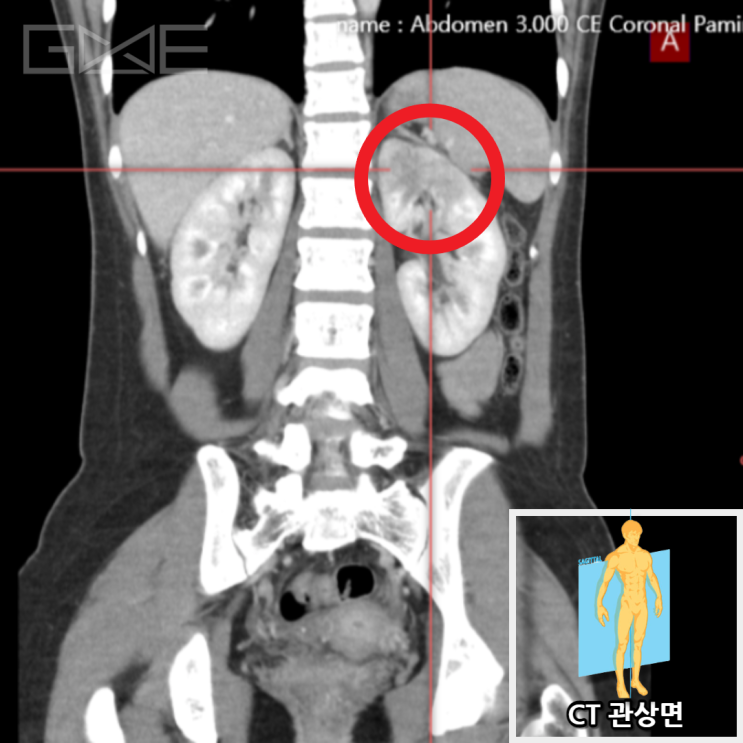

혈액검사 상에서 염증수치(CRP)의 심한 상승소견(19.21 mg/dL, 정상 0~0.5)이 확인되었습니다. X-RAY검사 상 발열 원인이 뚜렷하지 않았던 상태로 염증수치 상승소견에 대해 추가 검사 필요할 것으로 보여 CT 검사를 시행하였습니다. CT 검사 결과 왼쪽 신장에 염증소견으로 신우신염이 진단된 케이스입니다.

• 복부CT 관상면: 왼쪽 신장 염증소견(빨간 동그라미) 복부CT 관상면: 왼쪽 신장 염증소견(빨간 동그라미)